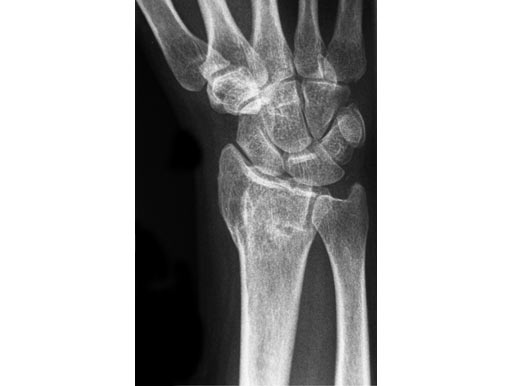

56-year-old female, accident at home